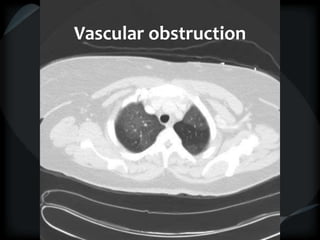

Mosaic CT Patterns

 Vascular obstruction

Airway obstruction

Vascular obstruction

CTPHTN